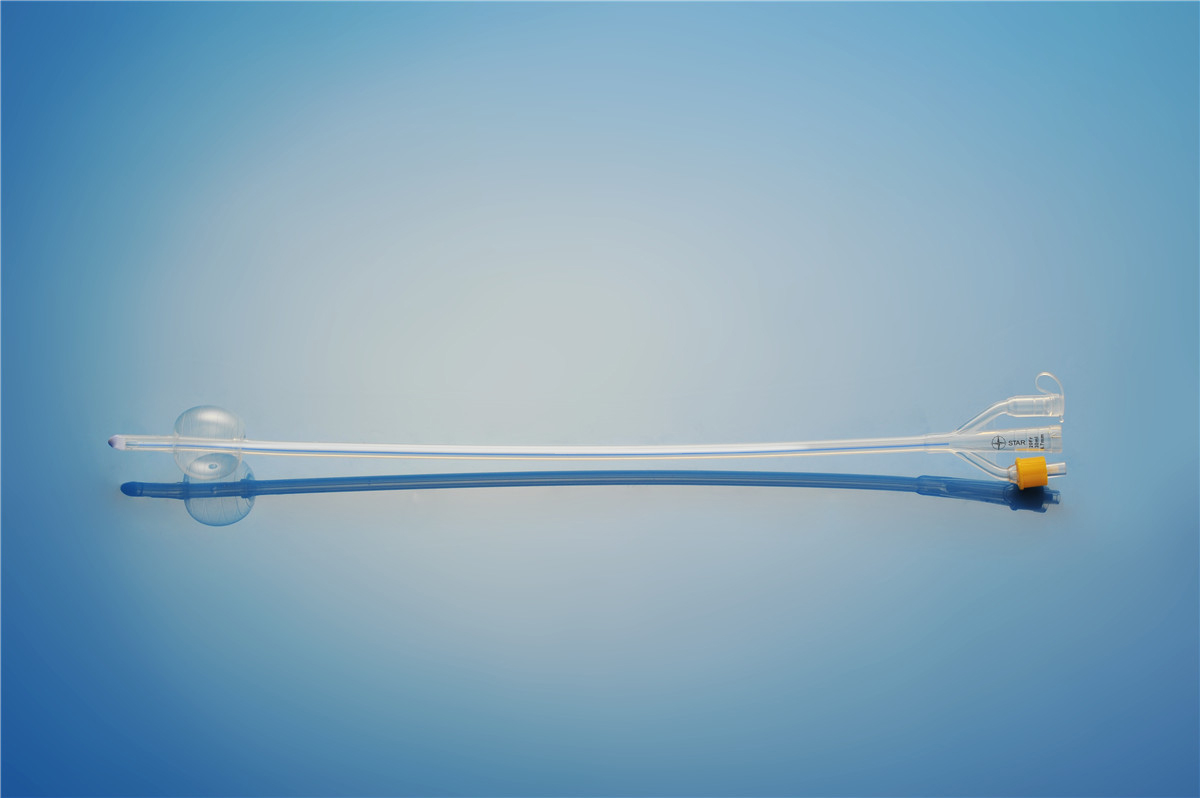

【產品名稱】一次性使用無菌導尿管(取樣型使用) 【型號】三腔氣囊取樣型 【規格】:16FR-26FR 【主要結構�、性能】由膠乳為主要原材料制成�,可配卡片。

型號:三腔氣囊標準型規格:三腔氣囊標準型:16Fr(30mL)、18Fr(30mL)���、20Fr(30mL)���、20Fr(50mL)、22Fr(30mL)���、22Fr(50mL)���、24Fr(30mL)、24Fr(50mL)�、26Fr(30mL)。結構及組成/主要組成成分:產品由導尿管����、水潤滑包(選配)組成。三腔由球囊腔充起錐...